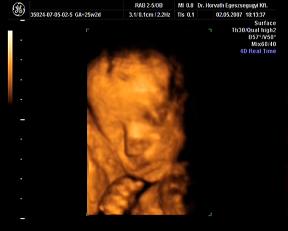

Néhány kép, nagyon kis drága volt, szépen mutatta magát:

egy 2D-s profil

És néhány 3D-s:

Kép Kép Kép Kép

Hát ilyenek vagyunk a 25. héten.:D